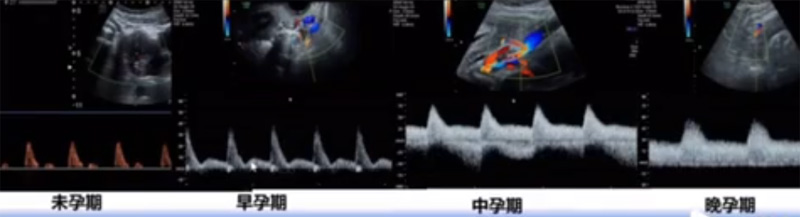

位于輸卵管的后下方,子宮兩側(cè)的后上方;借卵巢系膜與子宮闊韌帶后層相連。正常成人卵巢約4x3x2cm,跟睪丸的數(shù)值差不多,都是性器官,絕經(jīng)后卵巢萎縮變小、變硬。所以絕經(jīng)后婦女很難找到卵巢,主要功能:生殖和內(nèi)分泌功能分泌性激素。女性的第二性征。女性內(nèi)生殖器的血管分布,動(dòng)脈有子宮動(dòng)脈,卵巢動(dòng)脈,陰道動(dòng)脈,陰部?jī)?nèi)動(dòng)脈。靜脈它是與動(dòng)脈伴行。重要了解的是子宮動(dòng)脈,子宮動(dòng)脈是髂內(nèi)動(dòng)脈前干的重要分支,妊娠時(shí)候血流速度會(huì)增加的,為無創(chuàng)性檢查胎盤血管阻力的方法。未孕期頻譜為高阻力低舒張波形;正常妊娠時(shí)血流速度增加,血流阻力下降。